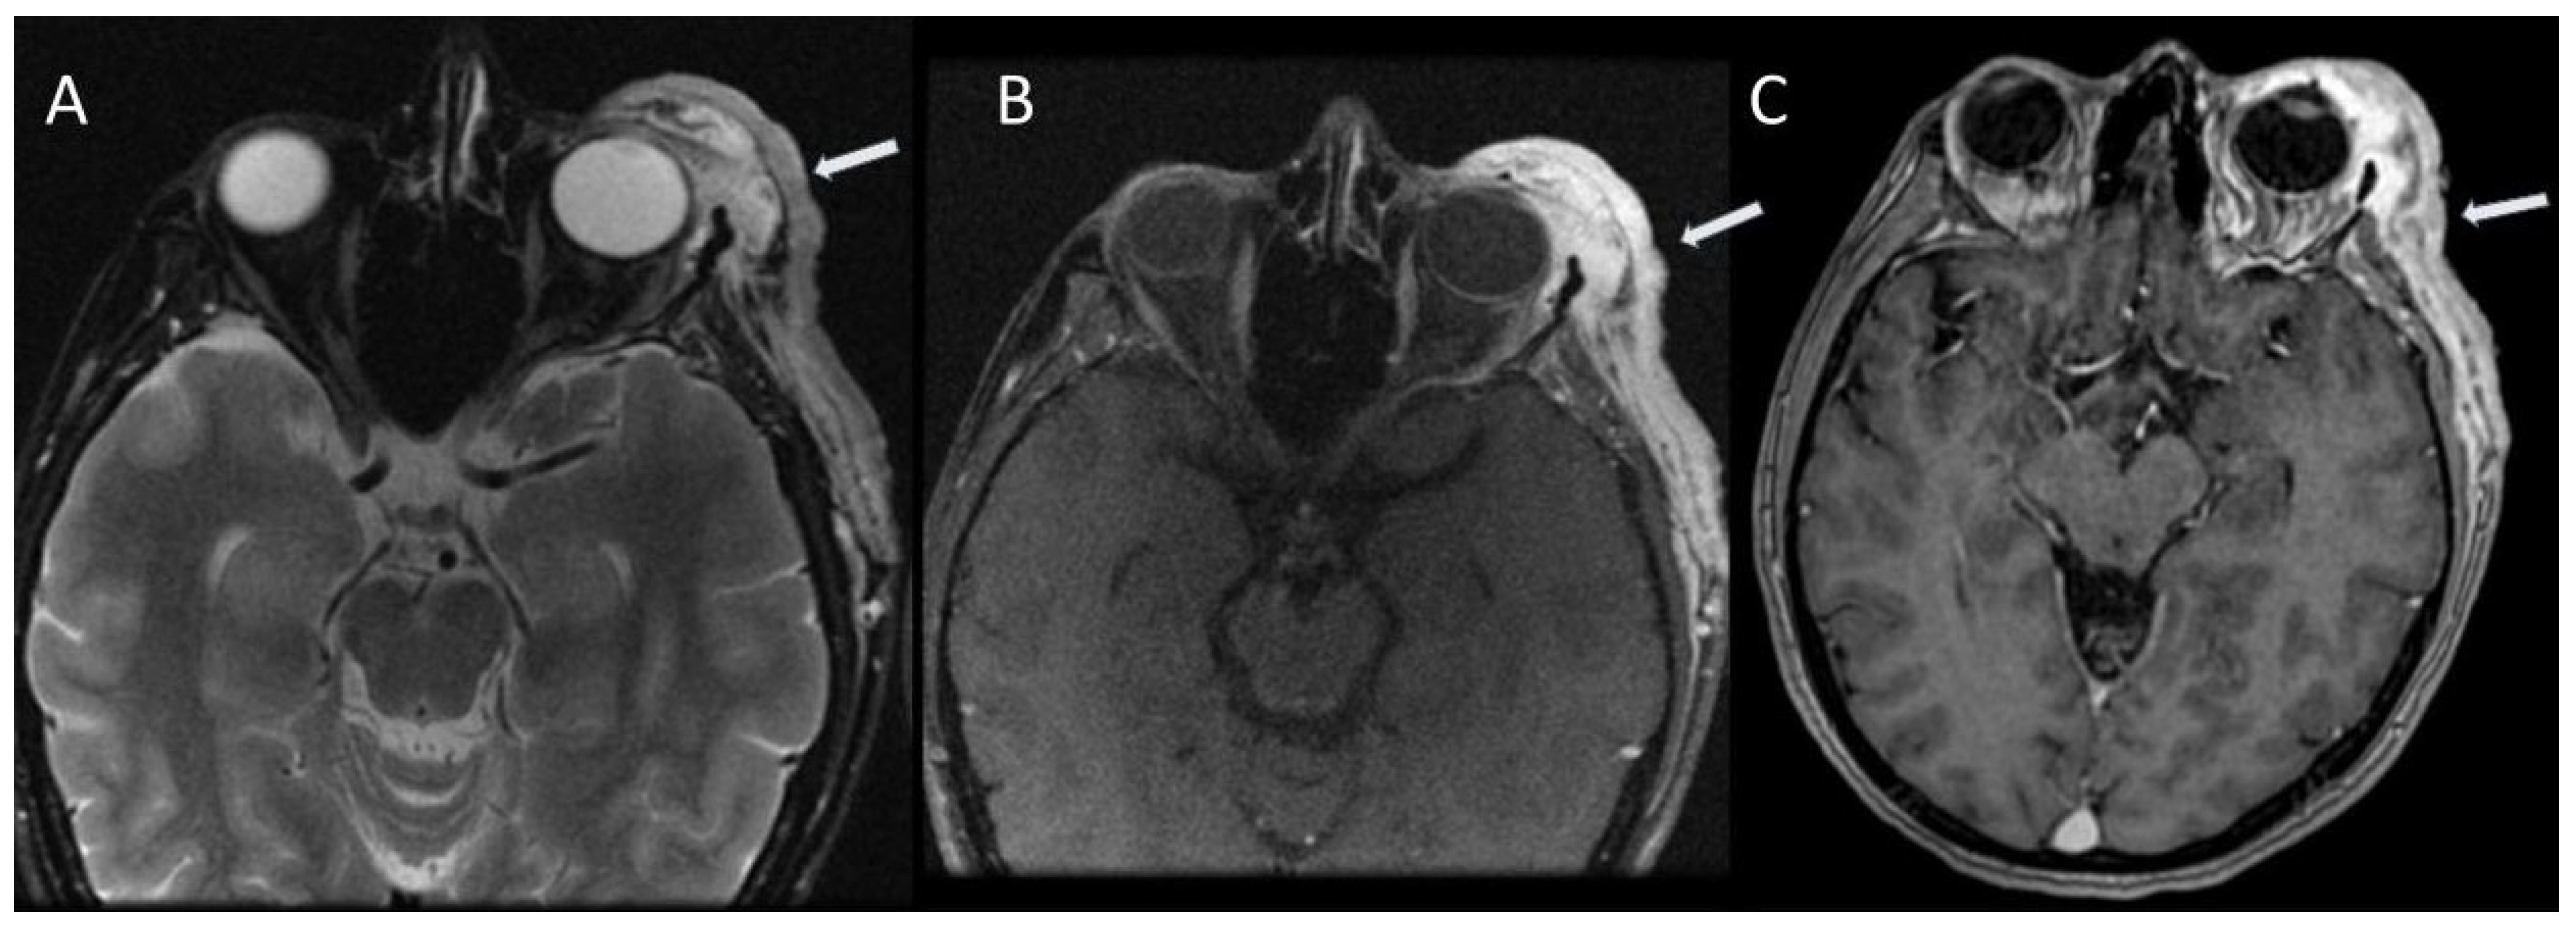

2.1. Visual Pathway Lesions

| Visual pathway lesions (optic pathway gliomas) | 5–15% | Enlargement of optic nerves or chiasma (diameter greater than 3.9 mm); |

| On T2-weighted images: compact low signal core with higher intensity circumferential component; | ||

| On T1-weighted images: isointense signal, with enhancement after gadolinium administration. | ||